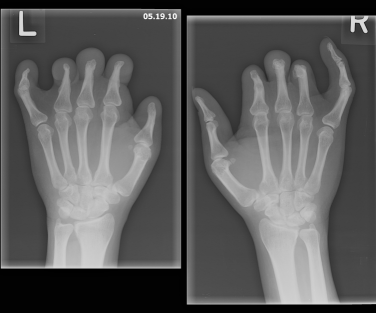

The patient was of short stature and had bilateral hand deformities in the form of extremely short nubbin-like second, third, and fourth fingers along with somewhat deformed thumbs. The fifth fingers of both hands demonstrated clinodactyly with partially hypoplastic nails (Figure 1). Radiographic images of both hands showed an absence of the middle and distal second, third, and fourth phalanges with tapering proximal phalanges and tapering of the distal fifth phalanx and distal first phalanx (Figure 2).

Figure 2. Radiographic images of the patient’s hands showed an absence of the middle and  distal second, third, and fourth phalanges with tapering proximal phalanges and  tapering of the distal fifth phalanx and distal first phalanx.